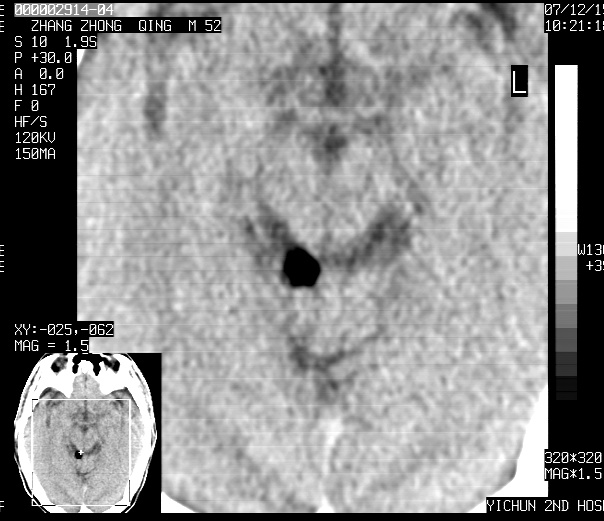

标题: CT11173:请会诊 男 52 [打印本页]

标题: CT11173:请会诊 男 52

不知ct值约多少,考虑四叠体池内脂肪瘤.

四叠体池脂肪瘤可能

1、四叠体脂肪瘤;

2、双侧额、顶部硬膜下积液。

头痛二年余,ct值-86.8hu.